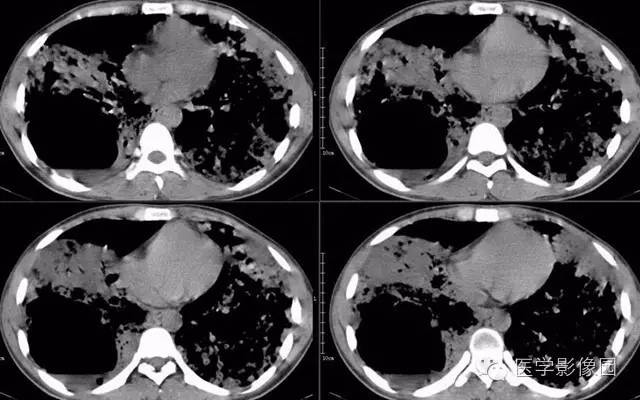

病理结果:弥漫性肺泡细胞癌

弥漫性肺泡癌的主要临床及CT表现:临床表现无明显特征, 随着病情的进展, 咳嗽、 咳白痰、 进行性气促。CT表现 为病变分布有两种情况:病变累及一个肺段或肺叶;病变广泛分布于两肺。可归纳为5个特征性征象:蜂房征;支气管充气征;磨玻璃征;血管造影征;两肺弥漫分布的斑片状与结节影。